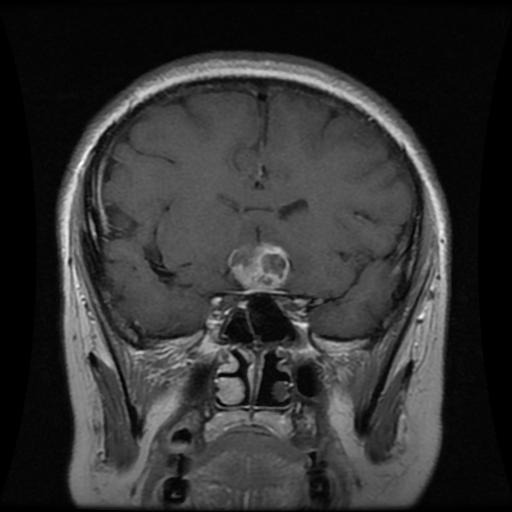

MRI brain scan input for AI diagnosis in Hospital Copilot. Apologies for no live demo due to setup limits.

AI analyzed MRI via Flask API; possible pituitary lesion detected. Apologies for no live demo due to deployment limits